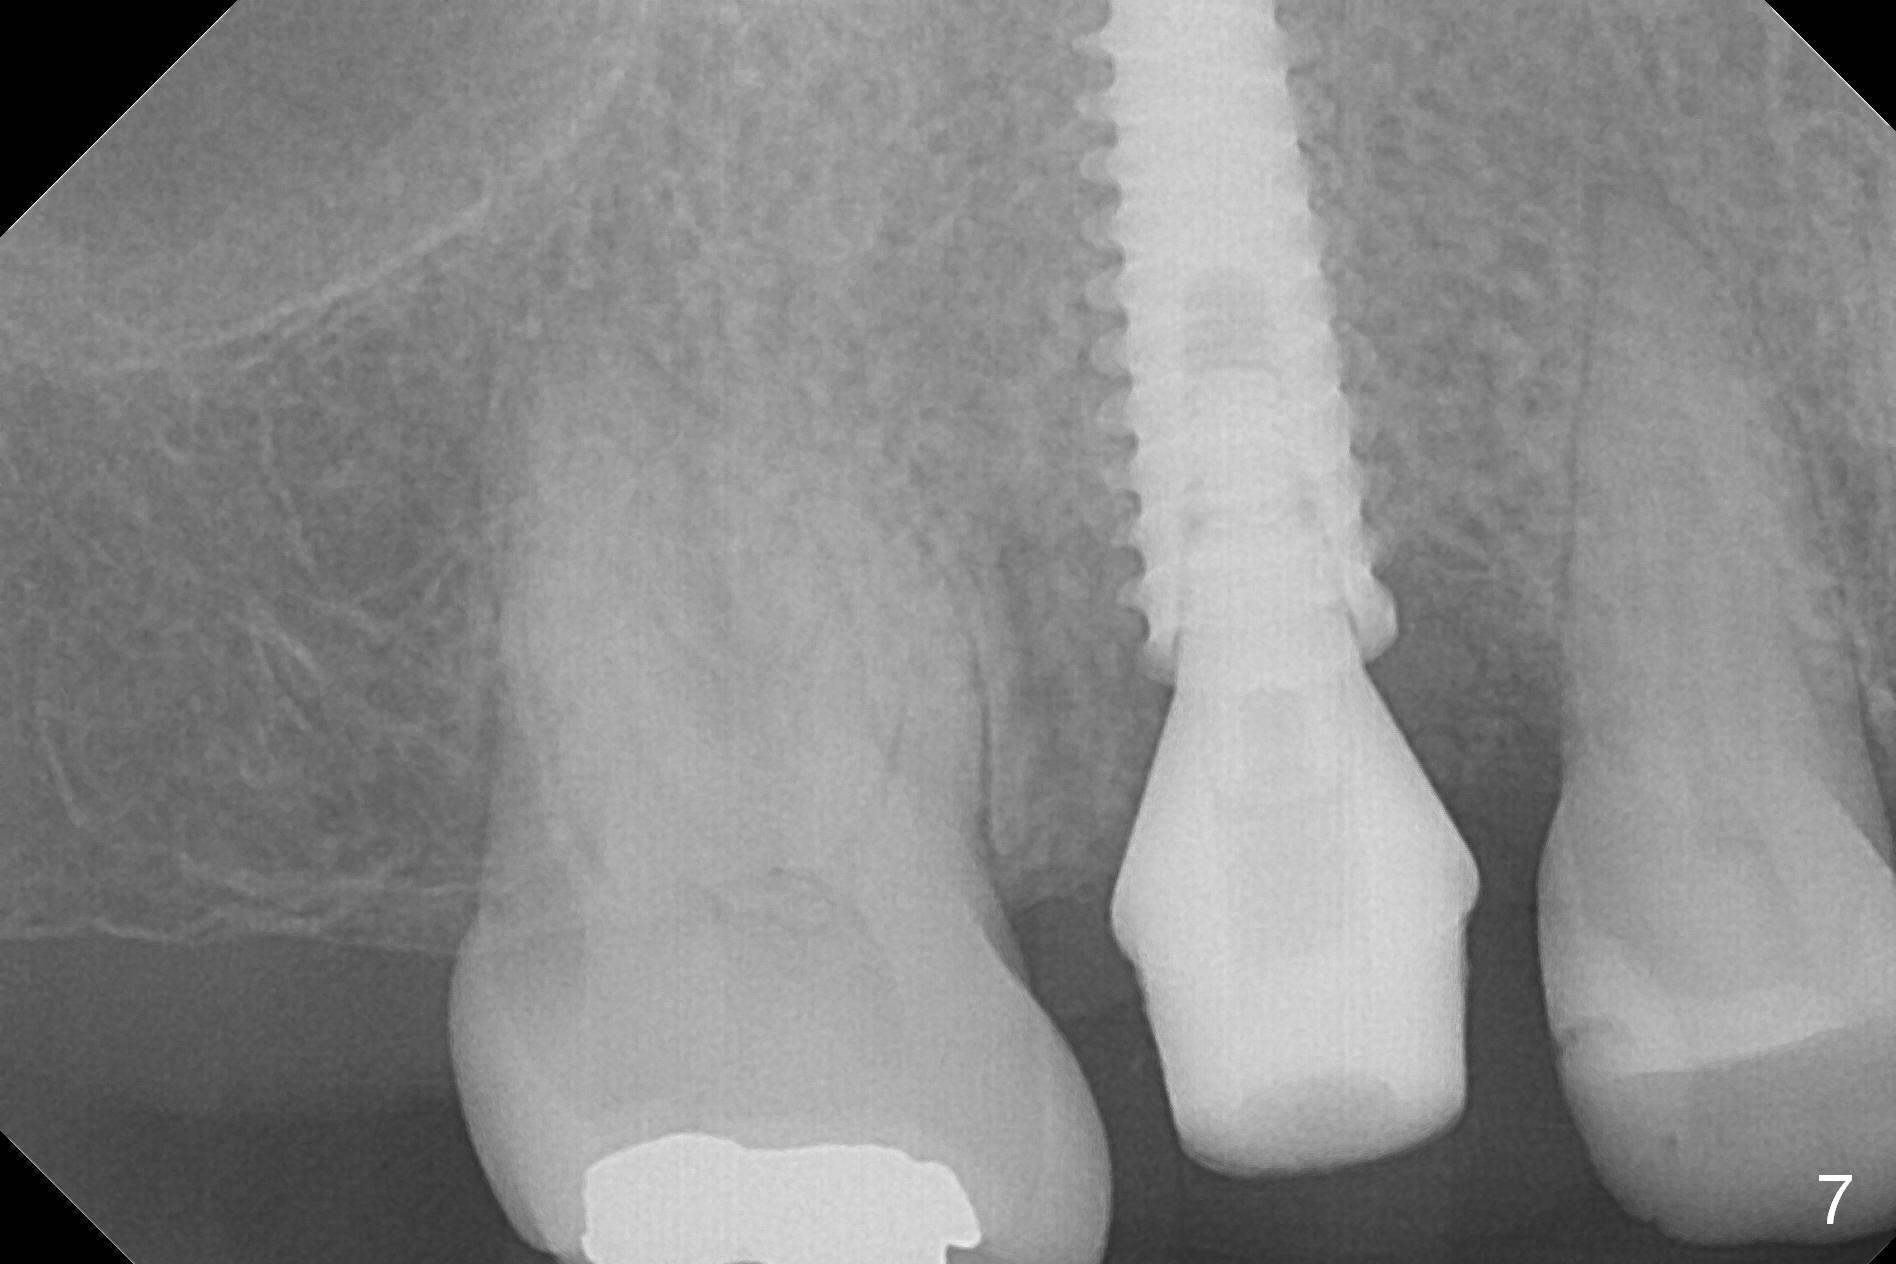

Three weeks postop, the socket has been healing with simultaneous buccal plate collapsing (Fig.5 *, as compared to Fig.2). A larger abutment (7.0-8.5 mm) or a provisional with buccal subgingival margin may decrease the postop shrinking (1,2). There is no bone loss 3 months postop (Fig.6,7). The screw needs to be retightened 9 months post cementation (Fig.8, when the tooth crown is being fabricated at #18). Unilateral mastication is a predisposing factor, since the tooth #19 is missing. When the crown becomes loose again 3 years later, the hex fractures inside the implant. After its removal (Fig.9), a narrower abutment is placed for a new crown (Fig.10: 5x4(4) vs. 6.5x4(4) mm). The implant was placed deep enough without thread exposure; now with apparently complete abutment seating (Fig.11,12). The similar complication may recur due to refusal to have implant at #19 (fear of nerve injury).